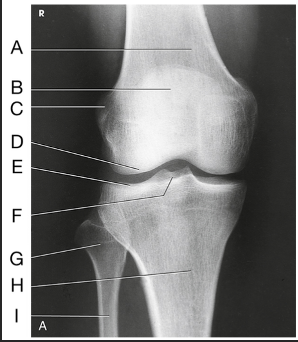

Label the image: A

popliteal surface

Label the image: B

adductor tubercle

Label the image: C

medial epicondyle

Label the image: D

medial condyle

Label the image: E

lateral condyle

Label the image: F

lateral epicondyle